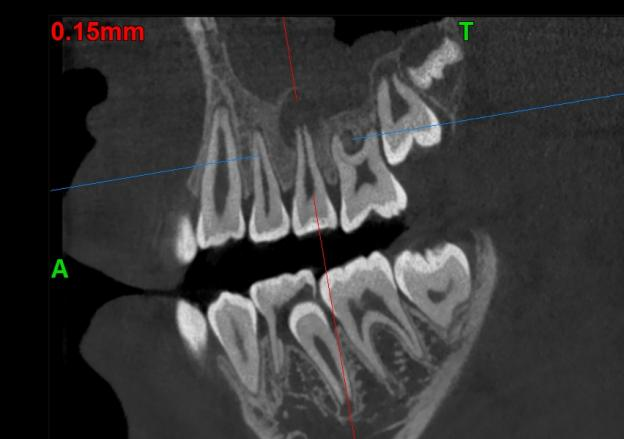

2个月后复查CBCT见充填物完好,根尖低密度暗影较前明显缩小

4个月后复查CBCT见充填物完好,根尖低密度暗影基本消失,根管长度较4个月前未见明显改变。